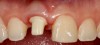

Plugging into digital workflows provides opportunities to integrate CAD/CAM technologies at every step of the treatment process for dental implants. In another example, a patient presented with a failing tooth No. 8 (Figure 6 and Figure 7). After discussing treatment options, the patient chose to forgo any treatment to address tooth and soft-tissue asymmetries and wanted to proceed with a dental implant-supported restoration without additional treatment. After integrated 3-dimensional planning, the tooth was extracted, and then an implant and the final custom CAD/CAM abutment (titanium base with zirconia supra-structure) were placed with a provisional restoration in the same visit (Figure 8 and Figure 9). Soft-tissue grafting was also done at the same visit to address the deficient buccal tissue height on No. 8 (Figure 10). At 3 months, the patient presented for the final restoration, with excellent healing around the implant (Figure 11) and soft-tissue healing guided by the custom abutment (Figure 12).

Fig 6. Clinical presentation of patient with a failing tooth No. 8.

Figure 6

Fig 7. Preoperative radiograph showing previous endodontic therapy on tooth No. 8.

Figure 7